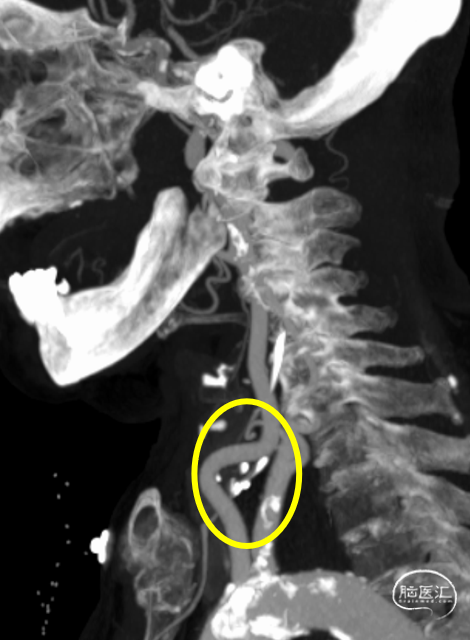

动脉晚期冠状位脑膜支逆流

动脉晚期矢状位脑膜支逆流

颈总动脉迂曲

颈内动脉